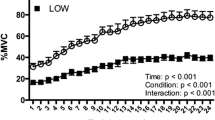

The present study was undertaken to investigate in a randomized controlled trial the effects of chronic (10 weeks, 4 h per day, 7 days per week) low-frequency (15 Hz) stimulation (CLFS) of the knee extensor and hamstring muscles of both legs in healthy volunteers via surface electrodes. A control group (n=10) underwent the same treatment (sham stimulation) as the CLFS-treated group (n=10), except that stimulation intensity was kept at a level which did not evoke contractions. Biopsy samples were taken before the onset and after cessation of stimulation from the right vastus lateralis muscle of all subjects. The biopsy samples were analyzed for changes in myosin heavy chain (MHC) isoforms and activities of citrate synthase (CS) and glyceraldehyde phosphate dehydrogenase (GAPDH) as markers of aerobic-oxidative and anaerobic pathways of energy metabolism, respectively. In addition, functional properties, i.e., oxygen consumption (V̇O2) and work capacity, were assessed. Sham stimulation did not affect the functional properties and had no detectable effect on MHC isoform and enzyme activity patterns. Conversely, CLFS induced changes in the MHC isoform pattern in the fast-to-slow direction with a ~20% decrease in the relative concentration of MHCIId/x (from 28% to 22%) and a ~10% increase in the relative concentration of MHCI (from 30% to 34%). In addition, CLFS led to a ~9% increase in the activity of CS concomitant with a ~7% decrease in the activity of GAPDH. This increase in aerobic-oxidative capacity was accompanied by improved work capacity and V̇O2 at the anaerobic threshold by 26% and 20%, respectively.